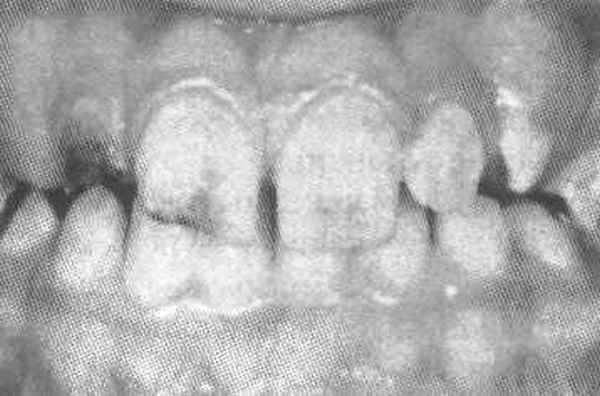

Общие сведения из анамнеза двух сестер: молочные зубы были серые, полупрозрачные и очень хрупкие. Наблюдалась задержка физиологической резорбции корней, поэтому молочные зубы удалялись. Кариесом временные зубы не поражались и никогда не болели. Постоянные зубы прорезались в нормальные сроки, но сразу же имели серый цвет и прозрачность (рис. 1а).

Рис. 1а. Зубы младшей сестры.

Уже в младшем школьном возрасте коронки постоянных зубов начали скалываться от физиологической нагрузки, в первую очередь шестые зубы. Границы сколов проходили по глубоким слоям дентина (рис. 2).